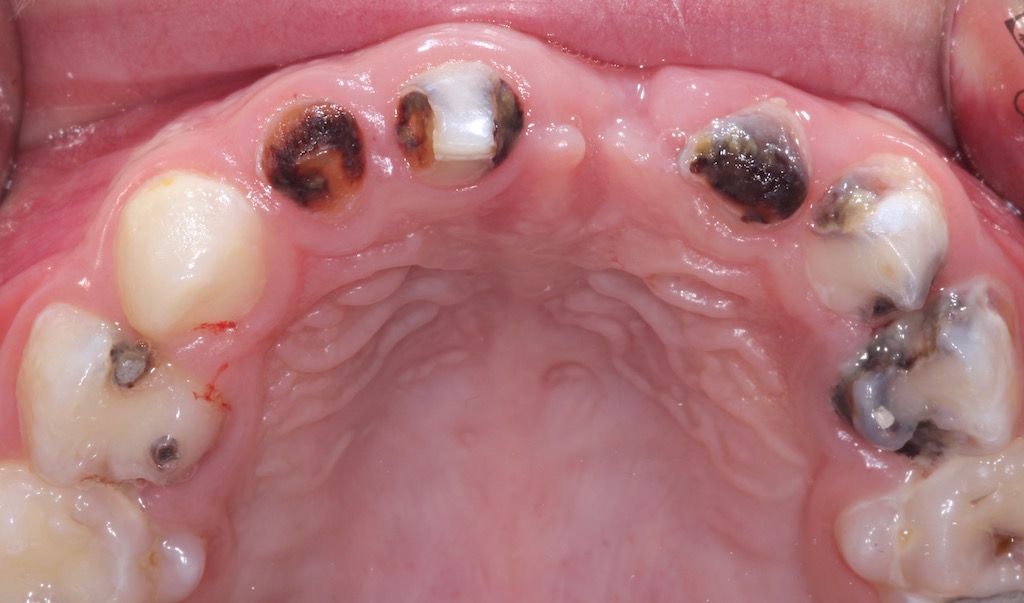

Beispielbefund: Das Bild zeight eine sogenanntes "Frühkindlichen Karies" (ECC) mit zahlreichen kariös befallenen Zähnen im Milchgebiss. Aufgrund der Dringlichkeit, des fortgeschrittenen Zerstörungsgrades der Zähne sowie des Patientenalters ist eine Behandlung in Intubationsnarkose indiziert.